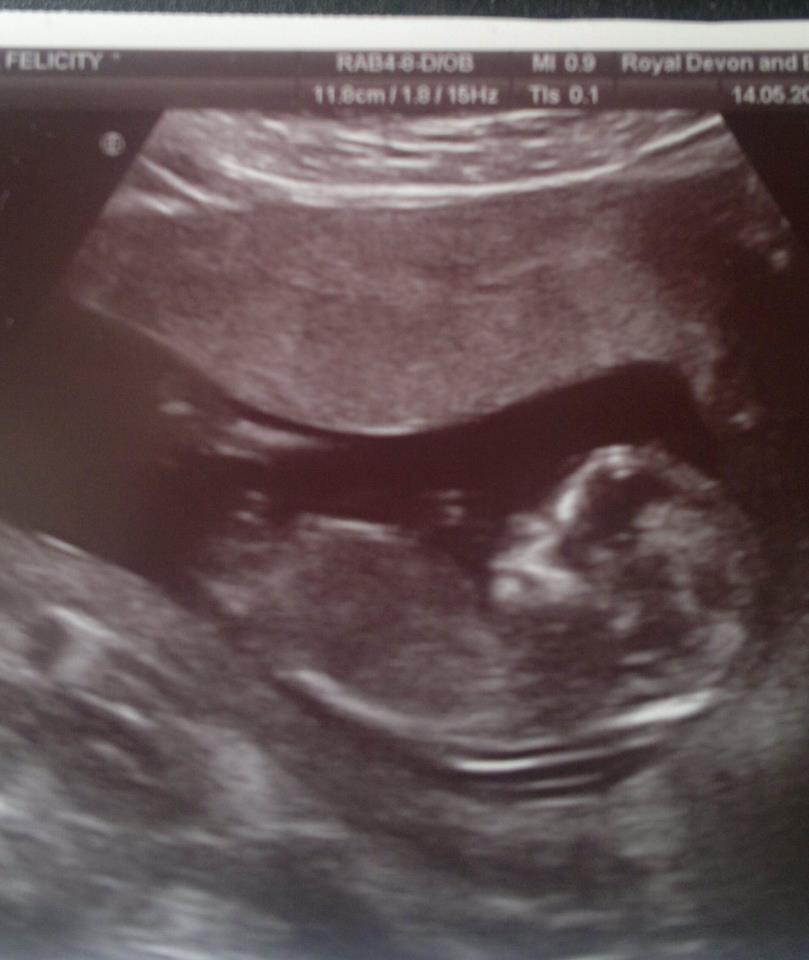

This is my scan at 13 weeks. Its not the clearest of pics but if you could take a guess it would be much appriciated :) Attachment 3001

I can't see THE NUB very good, but i think girl! Also based on skull en the angle. Tricky because it's a short one(or not shown totally) short normaly stands for boy...but i think GIRL!!!

I think maybe boy, but I'm not sure if what I'm seeing is the nub.

Not sure if that is the nub or cord.. if it's nub, boy, if it's cord - than 50/50